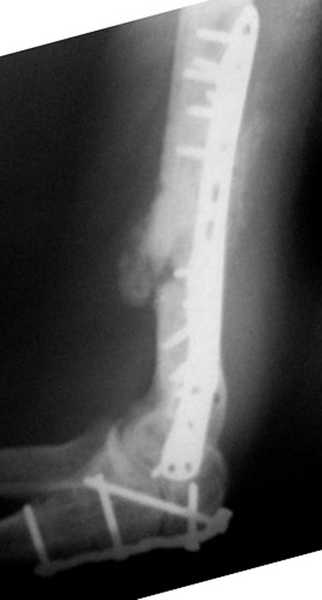

На примере два случая, извиняюсь за качество снимков, снимки и случаи из бывшего союза.

Первая больная с "успехом" была прооперирована 6 раз различными методами открытого и закрытого

остеосинтеза, включая то, что в Кисловодске заезжим австралийским "кудесником" на ложный сустав уложена скорлупа от страусиновых яиц. Последняя операция одиноким локинг плейт в одной из клиник.

Через год по поводу тех же проблем сделали ревизию, оригинальную пластину оставили как есть, только укрепили добавлением еще одной пластины и сделали костную пластику.

Через два месяца увидели признаки консолидации.

Второй случай, также после множественных операций:

пластина, аппарат, серкляж и парез нерва.

Также ревизия, из-за низкого состояния доступ был

сделан через остеотомию локтевого отростка.

Ложный сустав фиксирован двумя локинг плейт с

аутокостной пластикой, также через два месяца увидели признаки консолидации.

Движение в суставе разрешили в две недели.